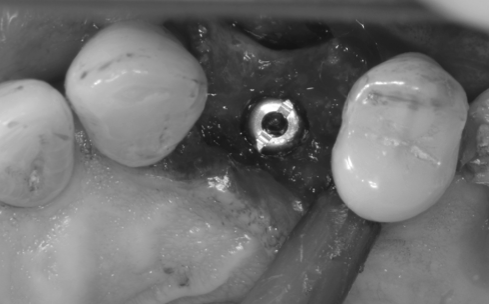

Apariția implanturilor dentare a dus la scăderea numărului de lucrări protetice mobilizabile (lucrări care se îndepărtează). După pierderea unui dinte se examinează vo lumul osos remanent, iar dacă osul este suficient se inseră implantul dentar, care este practic un înlocuitor pentru rădăcină (Fig. 3.5.1 și Fig. 3.5.2). Se așteaptă vindecarea pe o perioadă cuprinsă între 3 și 6 luni (Fig. 3.5.3). Se verifică radiografic poziționarea corectă a implantului (Fig. 3.5.4).